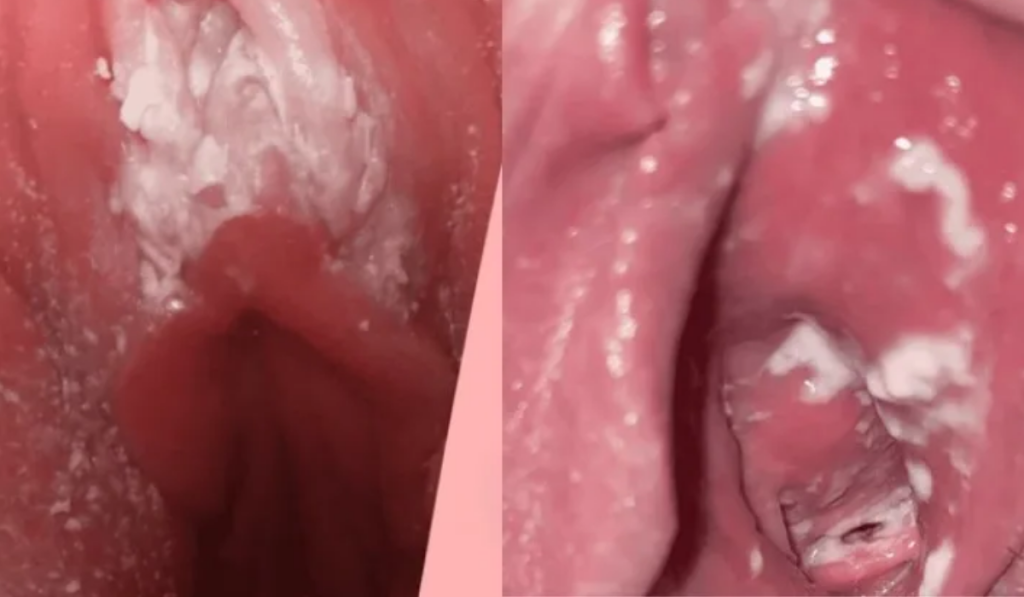

1. Hình ảnh ngứa do nhiễm nấm Candida

Đây là “thủ phạm” của hơn 80% các ca ngứa phụ khoa.

- Mô tả hình ảnh: Niêm mạc âm hộ, âm đạo đỏ rực, sưng tấy.

- Dấu hiệu nhận diện: Xuất hiện các mảng trắng đục bám dày vào thành âm đạo, khí hư vón cục như bã đậu hoặc giống váng sữa.

- Cảm giác: Ngứa dữ dội, đau rát khi đi tiểu hoặc khi quan hệ.